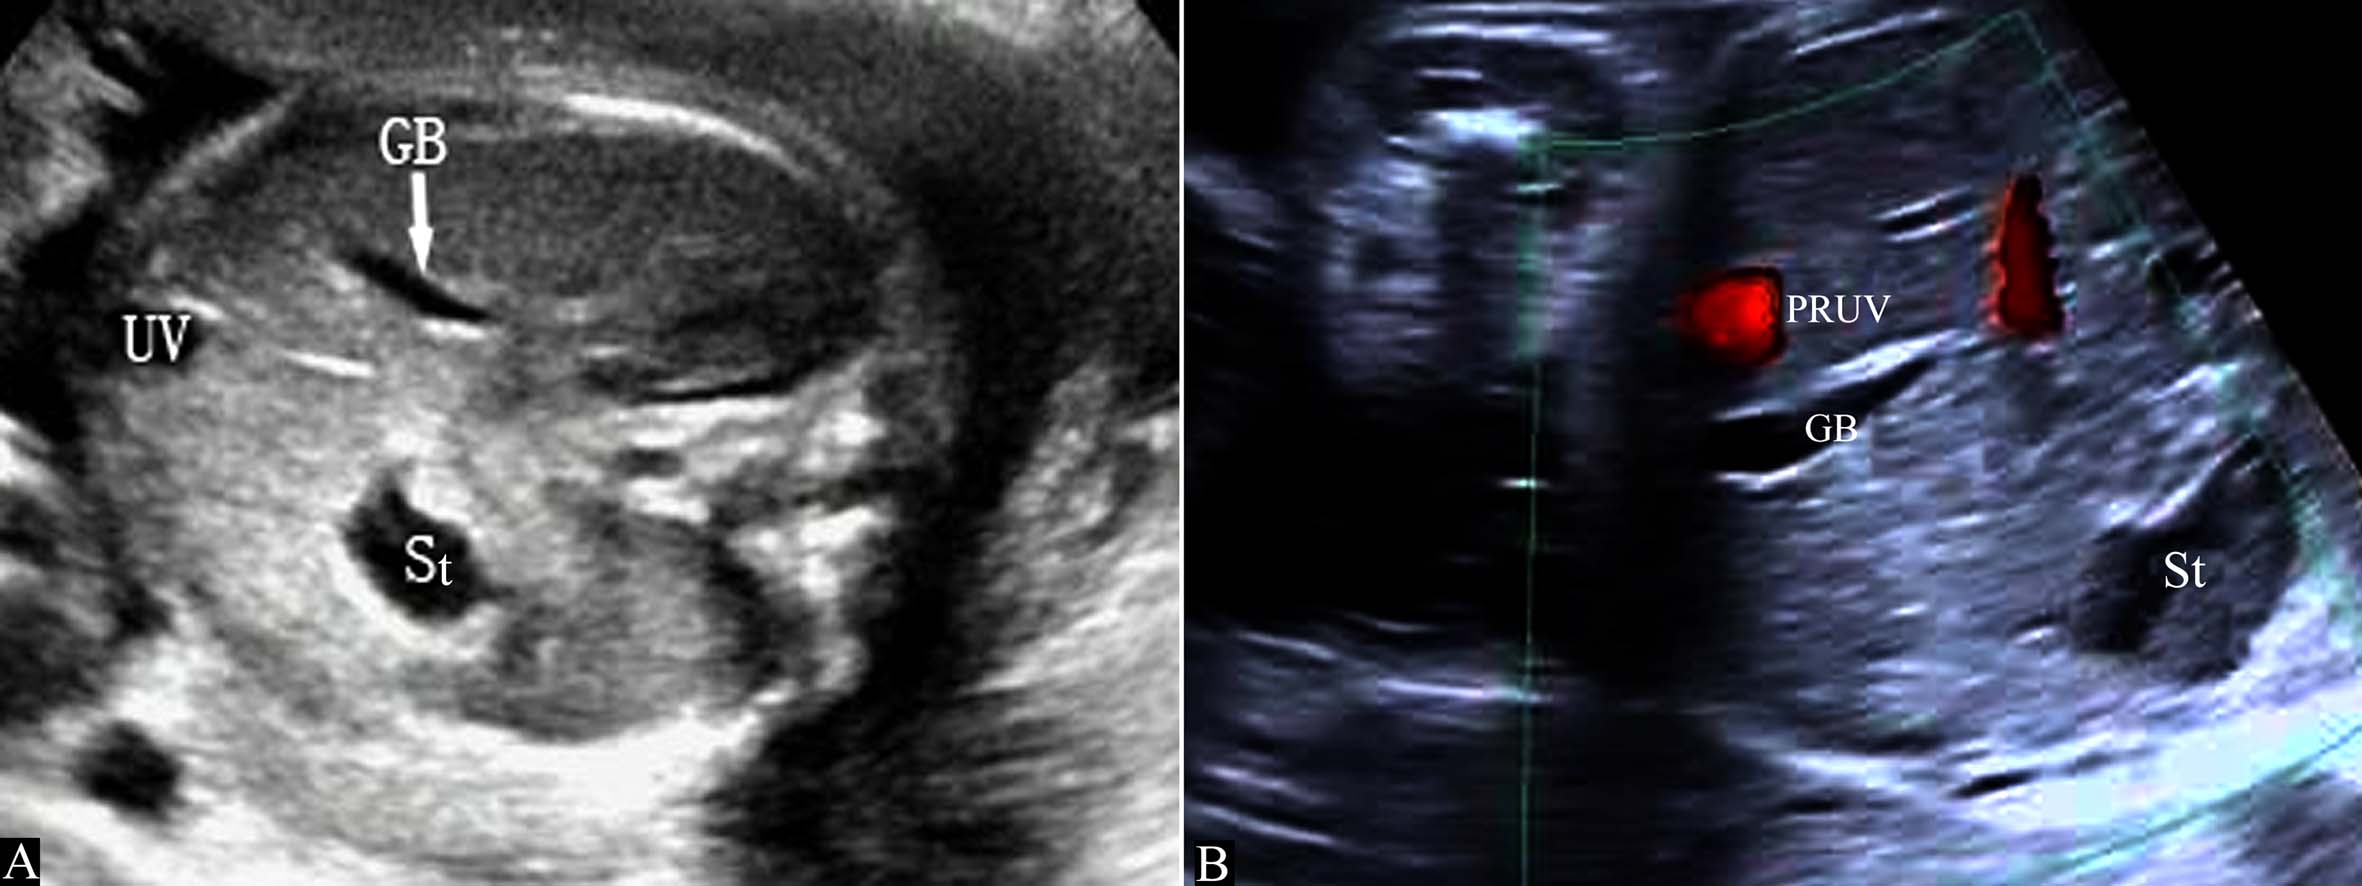

胚胎4周末右脐静脉开始闭锁,第7周时消失,形成正常的左脐静脉循环(图7A)。如右脐静脉不闭锁退化而左脐静脉闭锁,右脐静脉经过肝脏与静脉导管相连进入静脉导管,或绕过肝脏直接与下腔静脉或右心房相连(图7B),形成持续性右脐静脉7。在Hill等1994年进行的回顾性分析中,在15237例产科超声检查中发现了33例PRUV,产前超声检查显示率为0.21%(1:476);其中有18.2%(6/33)的伴有严重的先天性发育异常;在另一篇研究报道中,研究者在低风险胎儿中发现PRUV为1:526,其中17例胎儿合并其他部位的畸形,包括无脑儿、复杂性心脏畸形、双侧唇裂、孤立肾、单脐动脉等。

图7 持续性右脐静脉示意图

胎儿腹部横切面显示胃泡和脐静脉以后观察胆囊的位置可以确定脐静脉走行。正常脐静脉穿过脐轮后走行于胆囊的左侧,在胆囊与胃腔之间可以显示脐静脉的回声(图8A);如果在胆囊右侧显示脐静脉回声即可明确右脐静脉的诊断((图8B));肝内型持续性右脐静脉进入肝脏后PRUV需要转向左侧与静脉导管连接(图9)。连续追踪扫查如果显示脐静脉周围或一侧无肝脏实质,则提示为肝外型持续性右脐静脉。一般认为,后者常合并其他部位的发育异常,并可以合并染色体异常。

图11-54 持续性右脐静脉声像图